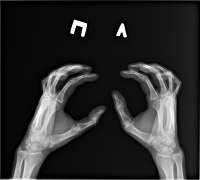

Сычевал всю жизнь со своим плоскостопием, из за тревоги и тряски начал шизеть и нашел утешение в ходьбе - стал ходить по 3-4 часа, зател решил что надо делать физуху и начал приседать, делать аэробику и даже с гирей дрыгаться.

Результат не заставил себя долго ждать - заныло колено, потом начало колоть, щемить и ныть сильней. Сидел дома месяц, вот теперь сделал рентген, пойду к врачу на след неделе. Походу пизда. Я так мечтал бегать, прыгать, но сука мудак ходил без ортопедической обуви и вот результат.

Аноним 17/02/24 Суб 23:46:42 1520799 50

> теперь сделал рентген

Кидай фотку